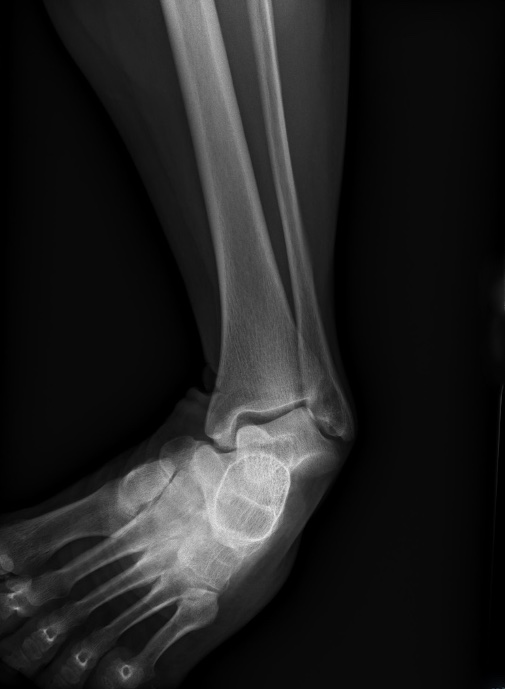

A 60 yo female presents with ankle pain after a fall from a ladder. On exam patient has a grossly deformed left ankle and an inverted foot. An xray is shown. What's the diagnosis? Scroll down for answer.

Answer: Comminuted fracture of the talus with medial dislocation of the subtalar joint. (Hawkins Type IV fracture of talus)

- AP xray will show medially displaced calcaneous as above and lateral will show talar head superior to navicular bone